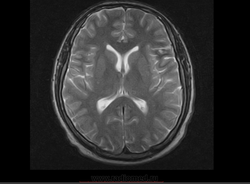

М, 27 лет. Жалобы на головные боли. ЧМТ в анамнезе. Стационар выставил внутримозговую гематому по КТ, полечили, отпустили.  К нам пришел на контроль.

Локализация таламус, граница коркового/мозгового, похоже на множественные кавернозные ангиомы. То, что в левой лобной?

Хочу посоветоваться с коллегами).  Дифференциальный ряд построить. Например токсоплазмоз, метастазы....в общем жду.

Сложно представить у молодого человека и каверномы, и метастазы одновременно.

Наверное, все же множественные каверномы, слева -осложненная кровоизлиянием.

Пришел к выводу, что сдесь все таки не каврномы, а мелкоочаговые кровоизлияния (ДАП). Учитывая травму и пребывание после этого  пациента в коме.